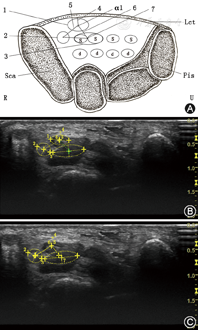

压力测量采用德国Zebris公司足底压力分布测量系统,检测到足底(手掌)压力的大小,通过计算机显示不同时间下压力的变化线图。超声测量采用美国GE公司LOGIQ E9超声诊断仪(图1A),该设备可对大量成像参数实现动态优化,将超声图像与其他成像技术如CT和MR的图像融合,能较精确地测量腕管内部神经、肌腱及其附属结构的参数指标。

检查部位为腕管近端的豌豆骨截面,手部体位设计有3种:(1)手部正常超声检查体位(体位①下,模拟不用力虚握鼠标,手掌朝上,与实际手握鼠标姿势相差180°)(图1B);(2)模拟垂直用力握鼠标体位(体位②下,掌指关节紧贴鼠标正上面,掌面呈水平面,并用90°直尺紧贴前臂,前臂呈铅垂线,使其垂直施加压力)(图1C);(3)模拟横向用力握鼠标体位(体位③下,手握鼠标掌面与水平面垂直,与实际手握鼠标姿势相差90°,掌指关节斜下用力,同时用45°三角尺一端紧贴第五掌指关节,另一端紧贴尺骨鹰嘴,使手臂与水平面保持45°)(图1D)。鼠标型号为华硕UT220收线蓝光光学鼠标,长宽高分别为95、57、36 mm。手部三种体位均置于水平放置的Zebris压力测试板上的鼠标垫,LOGIQ E9超声诊断仪的超声探头均垂直置于腕管近端的掌侧部位,微调方向直至超声显示屏对象图像清晰可见。

测量前培训志愿者,适应三种体位下的实验流程,拍摄实验图。实验按体位①、②、③的顺序进行。首先测量体位①,按常规超声检查指南测量豌豆骨截面的腕管内神经肌腱及其附属结构指标。其次,测量体位②、③。测量时,超声仪、压力测量仪操作者及志愿者准备就绪。(1)超声仪操作者发号施令,志愿者和压力测量仪及超声仪操作者同时开始实验,实时同步。志愿者在压力测量仪上缓慢加力,20 s内由0 N加到50 N并维持数秒。(2)压力测量仪操作者在压力测量系统中找到0、25、50 N对应的时间节点,并告知超声仪操作者(图1E)。(3)超声仪操作者根据对应时间节点在超声仪上分别测量各指标数值。每次实验开始前令志愿者微动拇指、第2至第5手指并观察超声仪屏幕中对应的部位,以明确测试部位的正确位置,并记录。

腕管内部神经、肌腱及其附属结构共有17个指标(图2),所有周长、长径、短径、距离等长度单位为厘米(cm),面积单位为平方厘米(cm2):(1)正中神经4个指标:周长C、面积A、长径d1、短径d2(cm);用LOGIQ E9超声诊断仪黄色虚线圈出,位于最靠近腕横韧带下方的低密度椭圆形1。(2)拇长屈肌4个指标:周长C、面积A、长径d1、短径d2(cm);用LOGIQ E9超声诊断仪左侧黄色虚线圈出,位于下方左侧的低密度椭圆形2。(3)指浅屈肌组4个指标(将与正中神经相邻的第2、3指浅屈肌看作一个指浅屈肌组):周长C、面积A、长径d1、短径d2;用LOGIQ E9超声诊断仪右侧黄色虚线圈出,位于下方右侧的低密度椭圆形3(包含第2、3指浅屈肌)。(4)正中神经与腕横韧带的距离D1:指从正中神经椭圆中心至垂直于腕横韧带的距离的黄色线段4。(5)正中神经与拇长屈肌的距离D2:指正中神经椭圆中心至拇长屈肌椭圆中心的距离的黄色线段5。(6)正中神经与指浅屈肌组的距离D3:指正中神经椭圆中心至指浅屈肌组椭圆中心(即第2、第3指浅屈肌的中点)的距离的黄色线段6。(7)指浅屈肌组和拇长屈肌的距离D4:指浅屈肌组椭圆中心至拇长屈肌椭圆中心的距离的黄色线段7。(8)正中神经与拇长屈肌及指浅屈肌组围成的三角形顶角α1(°):指正中神经椭圆中心、拇长屈肌椭圆中心、指浅屈肌组椭圆中心围成的三角形的顶角,位于正中神经黄色椭圆内。